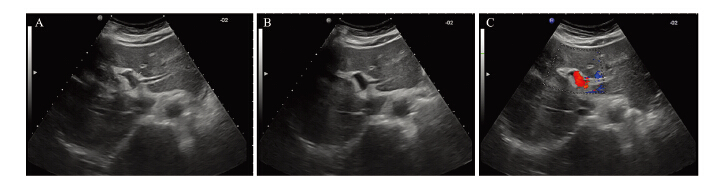

所有患者均按治疗计划顺利完成治疗。通过 超声和增强CT,观察瘤栓的分布范围、大小和 门静脉血流的变化。A组的近期有效率70.59% (24/34),B组的近期有效率67.74%(21/31), 两组疗效比较差异没有统计学意义(χ2=0.062, P=0.804),见表 2、图 2~3。

|

| A: main and right branch of PVTT before HIFU therapy;B:the tumor thrombosis disappeared after HIFU therapy;C: color Doppler rheography after HIFU therapy 图 2 Ⅱ级癌栓高强度聚焦超声治疗前后声像图 Figure 2 Contrast image of grade ⅡPVTT before and after HIFU therapy |